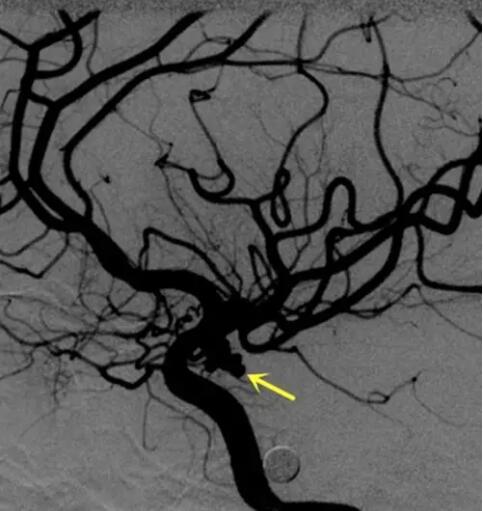

动脉瘤为什么号称颅内不定时炸弹!!!!!

随着生活水平和医疗技术水平的提高,颅内动脉瘤逐渐被大家所认识,那颅内动脉瘤有一个瘤字,它是肿瘤吗?其实,颅内动脉瘤不是我们通常意义上说的肿瘤,它只是指颅内动脉血管壁上的膨出,是由外膜和中膜组成的薄壁,因一般形态像气球一样的突出,有点类似肿瘤的样子,所以称之为颅内动脉瘤。初次破裂死亡率高达20%,极少病人能经历三次破裂。